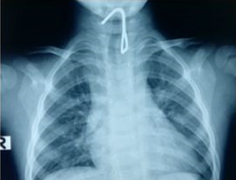

Thai nhi được thông van tim xuyên tử cung người mẹ đầu tiên ở Việt Nam chào đời sáng nay 30/1, bé khoẻ mạnh, nặng 2,9kg.